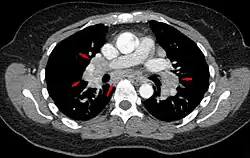

CT scan of the chest showing lymphadenopathy (arrows) in the mediastinum due to sarcoidosis

Diagnosis of sarcoidosis is a matter of exclusion, as there is no specific test for the condition. To exclude sarcoidosis in a case presenting with pulmonary symptoms might involve a chest radiograph, CT scan of chest, PET scan, CT-guided biopsy, mediastinoscopy, open lung biopsy, bronchoscopy with biopsy, endobronchial ultrasound, and endoscopic ultrasound with fine-needle aspiration of mediastinal lymph nodes (EBUS FNA). Tissue from biopsy of lymph nodes is subjected to both flow cytometry to rule out cancer and special stains (acid fast bacilli stain and Gömöri methenamine silver stain) to rule out microorganisms and fungi.[100][101][12][102]